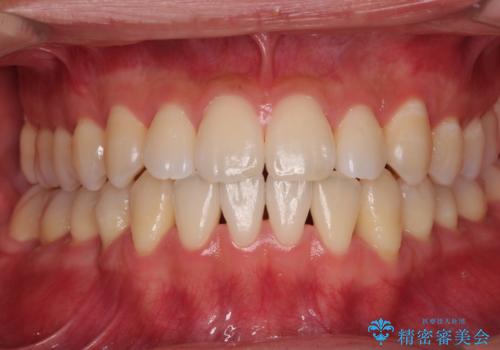

- 上下顎前歯部の非接触(開咬)と下顎のデコボコを主訴に来院された患者様です。

舌のトレーニングは継続して行ってもらっているため、開咬や抜歯したスペースの後戻りはなく、経過は良好です。